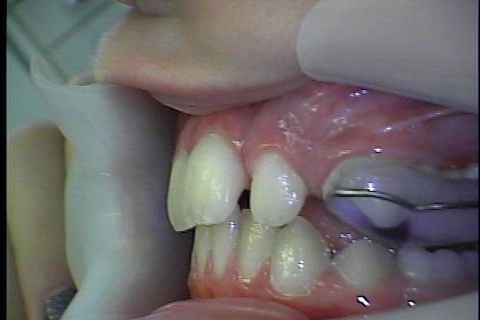

Instalaçao do disjuntor

Instalaçao do disjuntor para criar espaço

Disjunção realizada